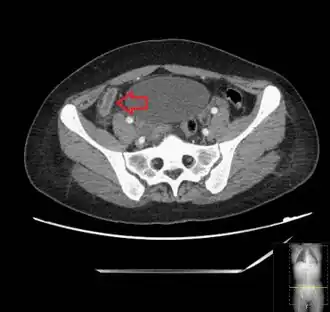

Computed tomography

Where it is readily available, computed tomography (CT) has become frequently used, especially in people whose diagnosis is not obvious on history and physical examination. Concerns about radiation tend to limit use of CT in pregnant women and children, especially with the increasingly widespread usage of MRI.[49][50]

The accurate diagnosis of appendicitis is multi-tiered, with the size of the appendix having the strongest positive predictive value, while indirect features can either increase or decrease sensitivity and specificity. A size of over 6 mm is both 95% sensitive and specific for appendicitis.[51]

However, because the appendix can be filled with fecal material, causing intraluminal distention, this criterion has shown limited utility in more recent meta-analyses.[52] This is as opposed to ultrasound, in which the wall of the appendix can be more easily distinguished from intraluminal feces. In such scenarios, ancillary features such as increased wall enhancement as compared to adjacent bowel and inflammation of the surrounding fat, or fat stranding, can be supportive of the diagnosis. However, their absence does not preclude it. In severe cases with perforation, an adjacent phlegmon or abscess can be seen. Dense fluid layering in the pelvis can also result, related to either pus or enteric spillage. When patients are thin or younger, the relative absence of fat can make the appendix and surrounding fat stranding difficult to see.[52]